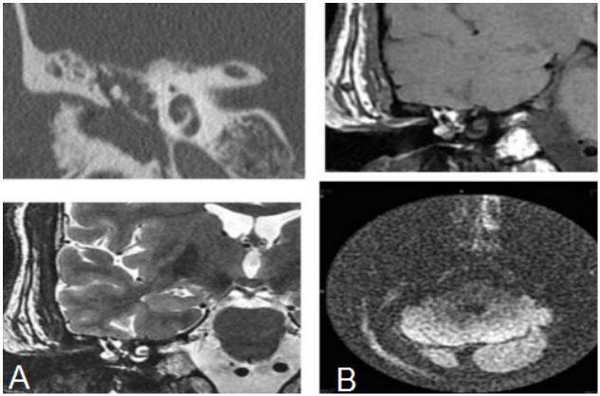

КТ (А) и МРТ(В) - картина холестериновой гранулемы

Эта дилемма волнует многих пациентов, но вид исследования выбирает лечащий врач, опираясь на результаты предыдущей диагностики и на конкретные жалобы. Отказываться от КТ уха из-за ложных соображений о вреде процедуры не стоит, современные мультидетекторные томографы позволяют минимизировать влияние лучевой нагрузки для большей категории лиц (исключение - беременные и дети, не достигшие 14 лет). В ряде наблюдений, особенно, если визуализируется опухолевый процесс, может понадобиться и МРТ, и КТ уха - эти способы взаимодополняют друг друга. Выполнение магнитно-резонансного сканирования обосновано, если после проведенной КТ остались сомнения в диагнозе. МРТ лучше демонстрирует менингоцеле, холестеатому, неврит лицевого нерва, внутричерепную патологию, вызванную процессами в среднем ухе, что не всегда показывает компьютерная томография высокого разрешения. КТ среднего уха часто не способна визуализировать степень возможной облитерации улитки после перенесенного воспаления или отдаленные последствия перелома височной кости. Точная оценка состояния имеет решающее значение для планирования кохлеарной имплантации.